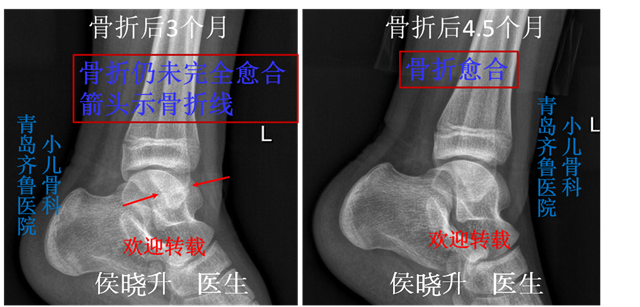

孩子脚扭伤了 当心是骨折 请及时到小儿骨科就诊 踝部扭伤 踝部扭伤